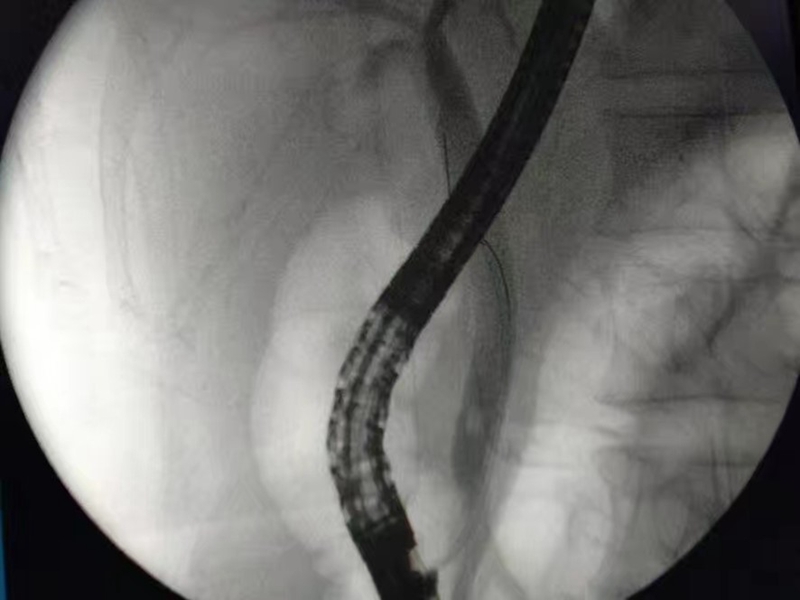

1.治疗性内镜逆行性胰胆管造影术(ERCP)

2.DSA下支架植入

开展DSA下食道支架植入术、十二指肠支架植入术、肠道支架植入术、食道气管瘘食道覆膜支架植入封堵术等等。